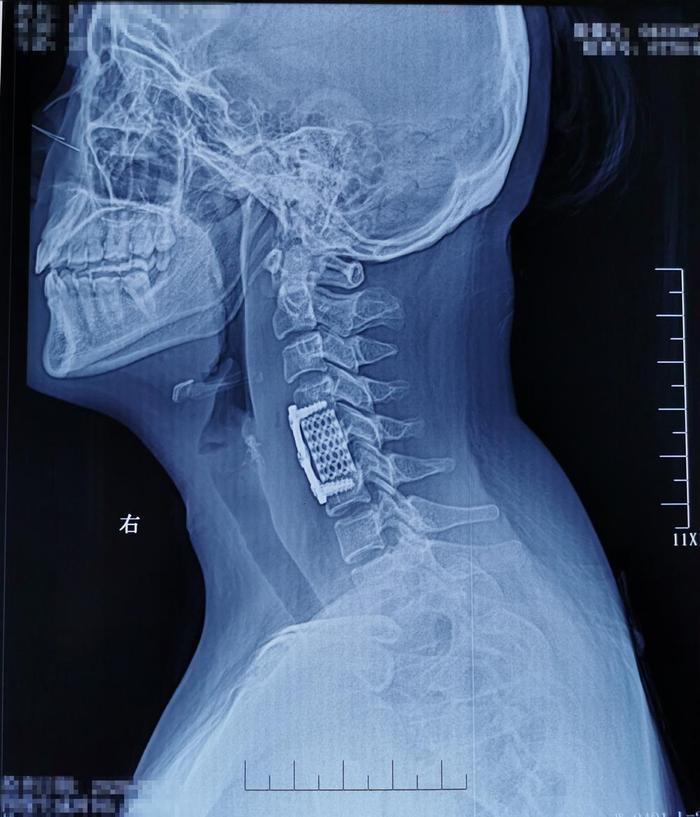

术后影像学资料:

病理结果示:颈5椎体结核。术后患者症状明显缓解,左上肢放散痛消失;目前已经康复出院,出院后给予正规抗结核治疗。